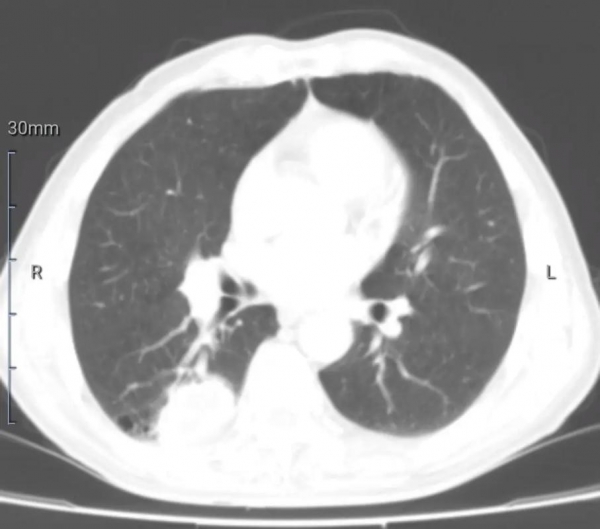

周先生,42岁,销售岗位,烟龄20年。每天两包烟,客户一到,烟就一根接一根。妻子劝、孩子哭、医生说--他都当耳边风。直到一次体检,肺部出现"异常影像",医生建议进一步检查。

那一刻,他才意识到,烟,不只是"习惯",而是可能随时带走健康的"隐雷"。他决定戒烟,哪怕很难。半年后,他回访时说:"没想到,我竟然开始闻得出饭菜香味了。"

10.肺部检查结果,可能出现"好转信号"

虽然肺部的结构性损伤不可逆,但戒烟后肺部炎症可能减轻,部分影像结果显示趋于稳定或改善。

体检时,医生可能告诉你:"肺纹理没再加重,挺好,继续保持。"